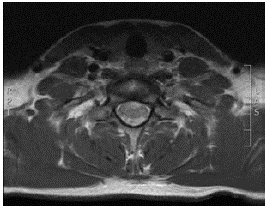

That same day, the patient was admitted to the Clinica Universitaria Colombia in Bogotá D.C. due to suspicion of transverse myelitis based on a feeling of stabbing pain in the thoracic spine, associated with hemiparesis of the left side of the body with predominance in the upper limb, mild respiratory difficulty, hyporeflexia and non-voluntary loss of 2kg of weight in 1 week. A cervical spine MRI was performed, showing an alteration in spinal cord signal intensity in the cervical segment, correlated with the affected cervical sensory level. This finding allowed diagnosing longitudinally extensive transverse myelitis (LETM) (Figures 1 and 2), so the patient was admitted to the hospital to start therapy with methylprednisolone pulses at a dose of 1g intravenously every 24 hours for 5 days. In addition, immunophenotyping and diagnostic studies were performed, obtaining negative LETM.

Contrast magnetic resonance imaging (MRI) of the cervical spine (axial plane) that shows spinal cord injury involving anterior horns with abnormal contrast uptake and contrast uptake of the roots, mainly anterior C5, C6, C7 and C8.

Figure 1: Contrast magnetic resonance imaging (MRI) of the cervical spine (axial plane) that shows spinal cord injury involving anterior horns with abnormal contrast uptake and contrast uptake of the roots, mainly anterior C5, C6, C7 and C8.

Source: Document obtained during the study.